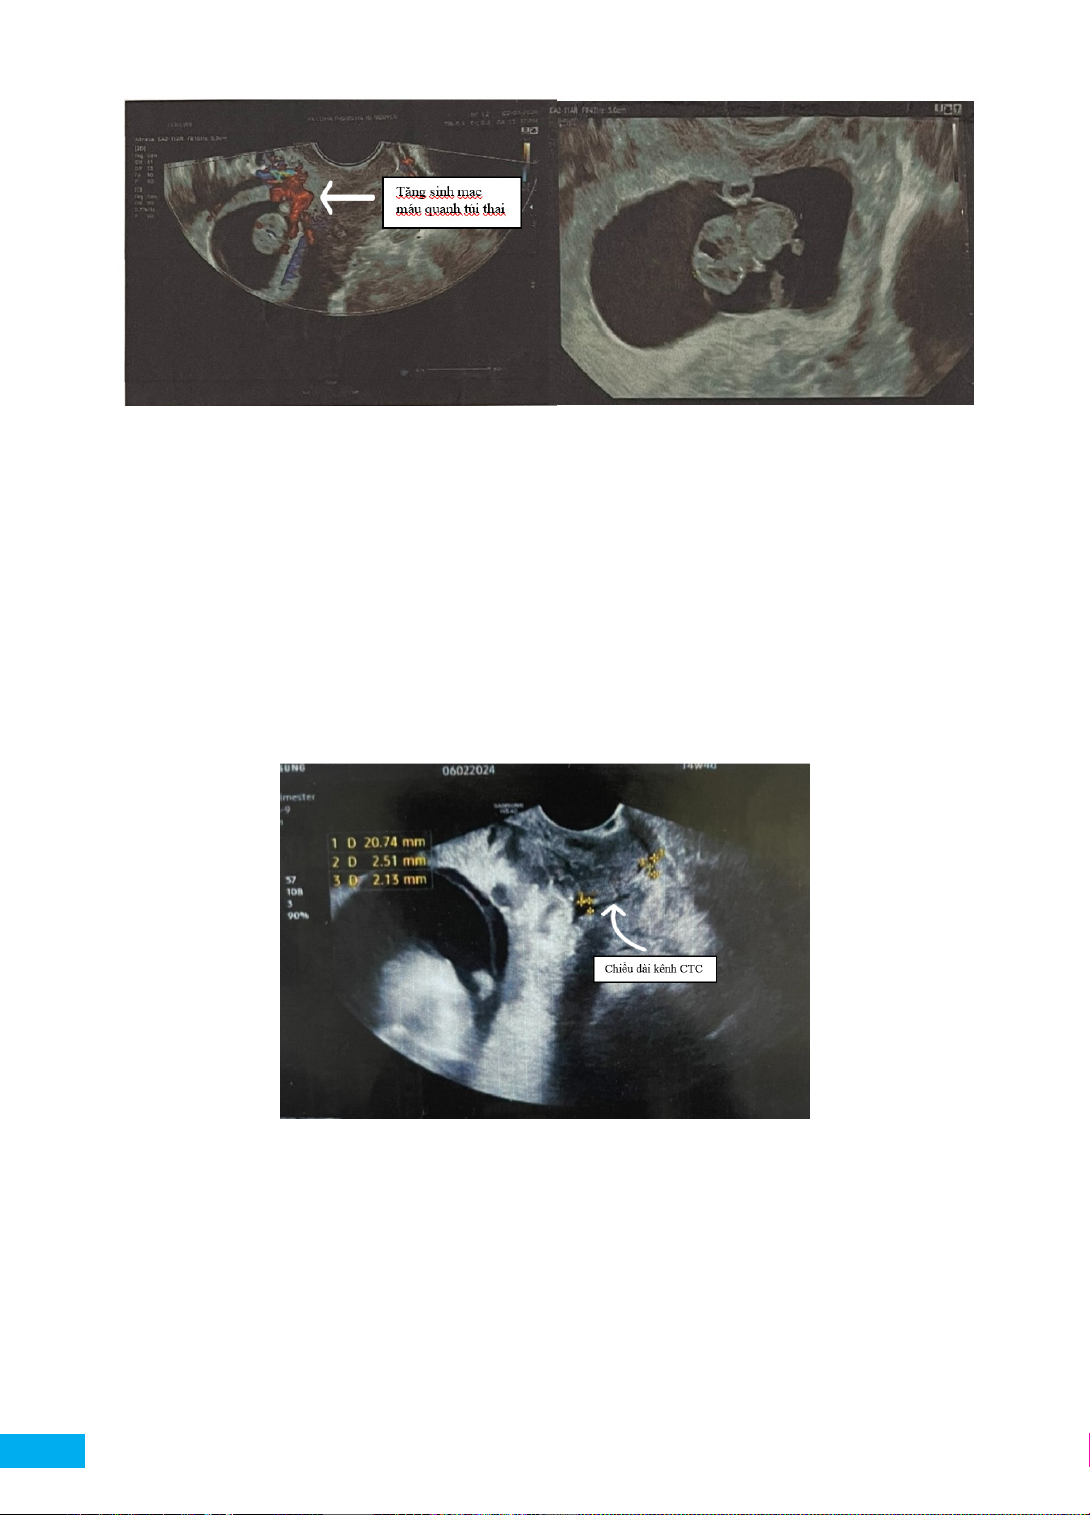

đến khám ở phòng khám chuyên khoa. Siêu âm (Hình

1) qua đường âm đạo (Máy siêu âm Samsung HS40).

Kết quả siêu âm cho thấy thai bám sẹo mổ lấy thai

khoảng 6 tuần, phân loại dấu bắt chéo trên siêu âm loại 1

(cross-over sign - COS -1). Bác sĩ tư vấn các nguy cơ của

TBSMLT, hướng dẫn bệnh nhân đến bệnh viện chuyên

khoa để thăm khám và chấm dứt thai kỳ.

Hình 1. Thai bám sẹo mổ lấy thai 6 tuần, phân loại dấu bắt chéo loại 1 (COS-1)

(Tử cung tư thế trung gian, đường kính trước sau 37,3 mm, buồng tử cung trống, nội mạc tử cung dày 10,6 mm,

hình ảnh khuyết sẹo mổ lấy thai kích thước 12,5 x 5,9 mm, một túi thai nằm tại phần eo thành trước tử cung ngay vị

trí sẹo mổ lấy thai, không lấp đầy hốc sẹo, trong túi thai có một phôi thai sống kích thước 2,8 mm, tim thai 123 lần/

phút (Hình 1). Buồng trứng bên phải bình thường, buồng trứng bên trái có nang đơn thùy kích thước 25 mm.

Túi cùng Douglas không có dịch. Hình ảnh siêu âm Doppler màu có tăng sinh mạch máu quanh túi thai)

Hình 2. Siêu âm thai 10 tuần, tăng sinh mạch máu tại vị trí TBSMLT

(Tử cung tư thế trung gian, buồng tử cung trống, kênh cổ tử cung trống nội mạc tử cung dày 15 mm. Vùng sẹo

MLT có một túi thai bờ không đều KT 43x44x48mm, bên trong có một phôi thai sống, có tim thai, chiều dài đầu

mông 15mm. Có > 2/3 túi thai nằm trên đường nội mạc về phía trước tử cung, còn cắt đường nội mạc tử cung. Bề

dày cơ tử cung giữa túi thai và bàng quang dày 1,8 mm. Chúng tôi không ghi nhận dấu hiệu trượt túi thai và có dòng

chảy trên Doppler quanh túi thai. Túi cùng Douglas không có dịch)